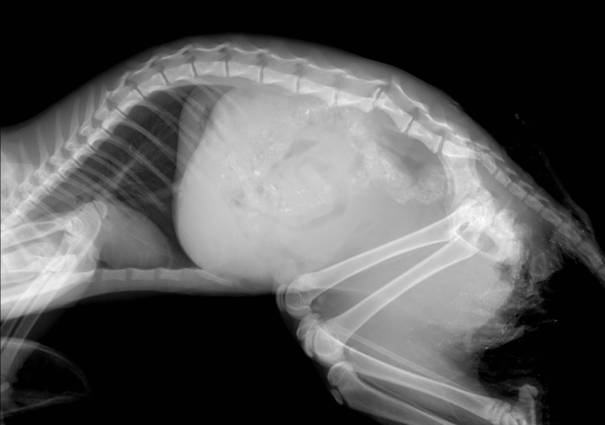

Рентгенологическая диагностика саркомы у кошек

Раздел: Визуальный дайджест